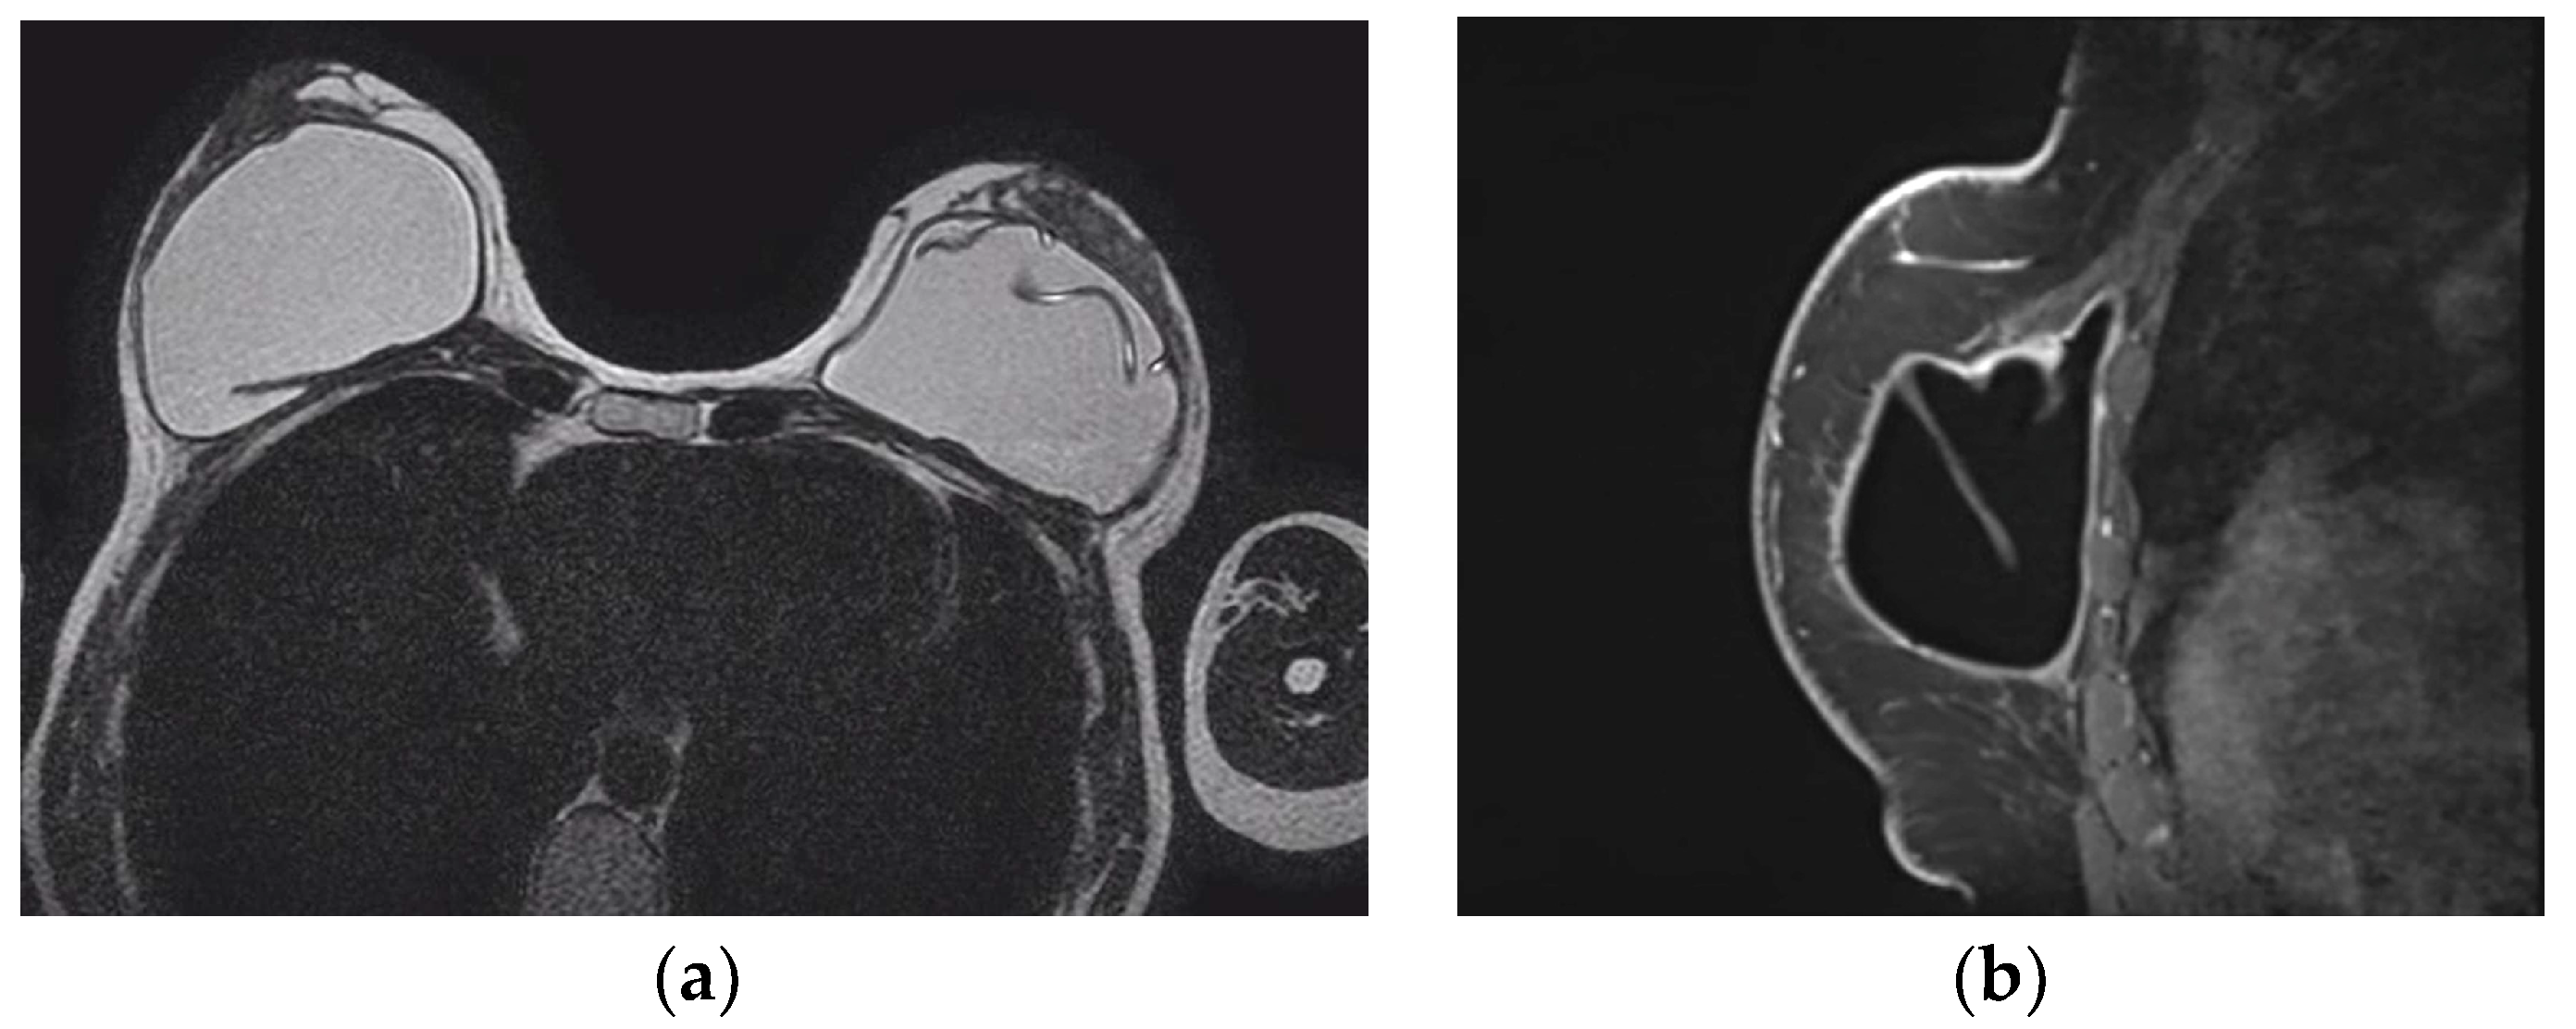

5.2.5. Implant Rupture

- Wong, T.; Lo, L.W.; Fung, P.Y.; Lai, H.Y.; She, H.L.; Ng, W.K.; Kwok, K.M.; Lee, C.M. Magnetic resonance imaging of breast augmentation: A pictorial review. Insights Imaging 2016, 7, 399–410. [Google Scholar] [CrossRef] [PubMed]

- Norena-Rengifo, B.D.; Sanin-Ramirez, M.P.; Adrada, B.E.; Luengas, A.B.; Martinez de Vega, V.; Guirguis, M.S.; Saldarriaga-Uribe, C. MRI for Evaluation of Complications of Breast Augmentation. Radiographics 2022, 42, 929–946. [Google Scholar] [CrossRef]

- Safvi, A. Linguine sign. Radiology 2000, 216, 838–839. [Google Scholar] [CrossRef]

- Soo, M.S.; Kornguth, P.J.; Walsh, R.; Elenberger, C.; Georgiade, G.S.; DeLong, D.; Spritzer, C.E. Intracapsular implant rupture: MR findings of incomplete shell collapse. J. Magn. Reson. Imaging 1997, 7, 724–730. [Google Scholar] [CrossRef] [PubMed]

- Maijers, M.C.; Niessen, F.B.; Veldhuizen, J.F.; Ritt, M.J.; Manoliu, R.A. MRI screening for silicone breast implant rupture: Accuracy, inter- and intraobserver variability using explantation results as reference standard. Eur. Radiol. 2014, 24, 1167–1175. [Google Scholar] [CrossRef]